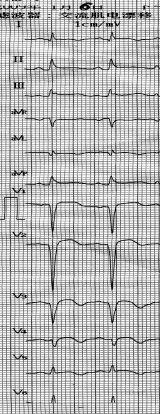

图1:A 2009年1月1日,术前ST段抬高;B 术后ST段回落。